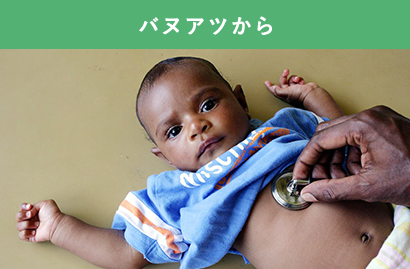

治療を受けて回復中の赤ちゃん